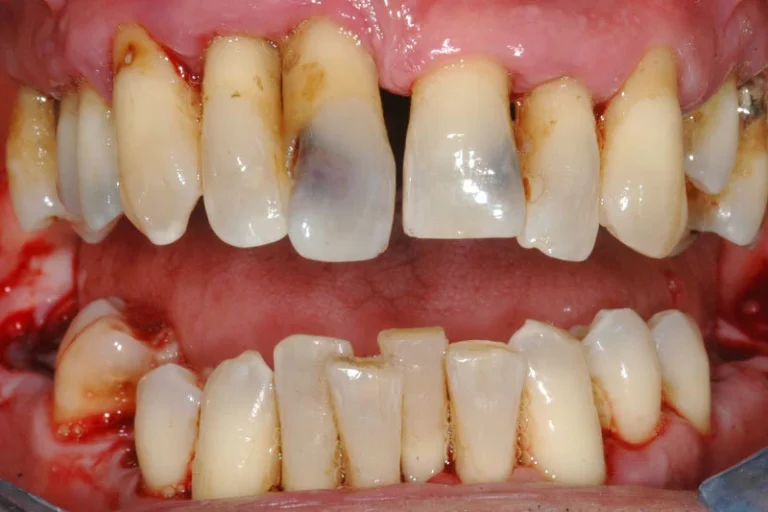

Dai singoli impianti alle riabilitazioni complete del cavo orale, Dentale Albania è la destinazione ideale per una trasformazione dentale in Albania.

L’odontoiatria generale include diagnosi, prevenzione e trattamento della salute orale.

Ogni intervento eseguito all'interno della tua bocca.